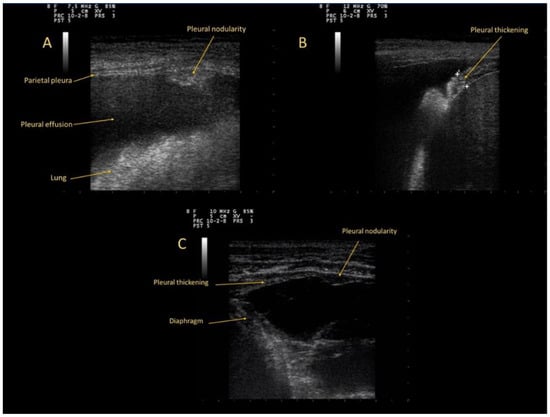

All patients underwent chest US examination. Pleural abnormalities in CPA were detected in 23 patients (82%). These abnormalities (Figure 1) were classified in: pleural thickenings (12 cases), nodularities (seven cases) and a combination pattern of nodules and thickenings (four cases). Each pattern was divided into two categories based on dimension: up to 5 mm, and ranging from 5 to 10 mm. (Table 2).

Figure 1. (A): Pleural nodularity; (B): Pleural thickening; (C): pattern of nodules and thickenings.